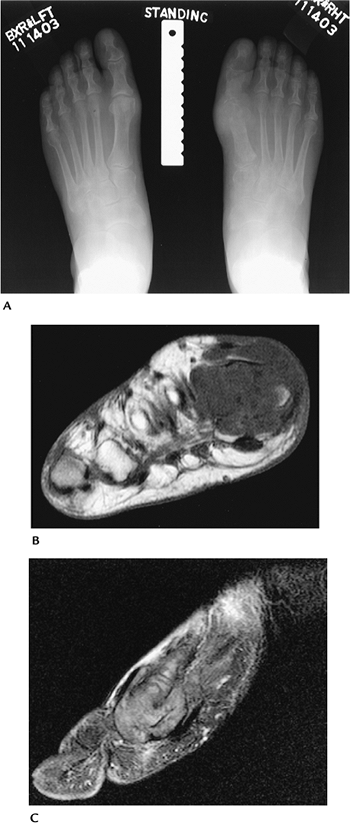

![]() |

FIGURE 13-28 Gout. (A)

Standing radiographs of the feet demonstrate bone destruction involving the distal first metatarsal and proximal phalanx on the right. (B) Axial T1- and sagittal post-contrast (C) fat-suppressed T1-weighted images demonstrate advanced bone and soft tissue changes of gout. |